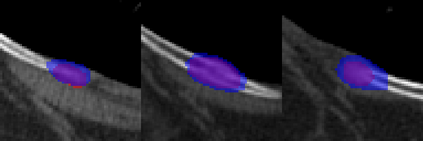

Rib fractures are a common and potentially severe injury that can be challenging and labor-intensive to detect in CT scans. While there have been efforts to address this field, the lack of large-scale annotated datasets and evaluation benchmarks has hindered the development and validation of deep learning algorithms. To address this issue, the RibFrac Challenge was introduced, providing a benchmark dataset of over 5,000 rib fractures from 660 CT scans, with voxel-level instance mask annotations and diagnosis labels for four clinical categories (buckle, nondisplaced, displaced, or segmental). The challenge includes two tracks: a detection (instance segmentation) track evaluated by an FROC-style metric and a classification track evaluated by an F1-style metric. During the MICCAI 2020 challenge period, 243 results were evaluated, and seven teams were invited to participate in the challenge summary. The analysis revealed that several top rib fracture detection solutions achieved performance comparable or even better than human experts. Nevertheless, the current rib fracture classification solutions are hardly clinically applicable, which can be an interesting area in the future. As an active benchmark and research resource, the data and online evaluation of the RibFrac Challenge are available at the challenge website. As an independent contribution, we have also extended our previous internal baseline by incorporating recent advancements in large-scale pretrained networks and point-based rib segmentation techniques. The resulting FracNet+ demonstrates competitive performance in rib fracture detection, which lays a foundation for further research and development in AI-assisted rib fracture detection and diagnosis.